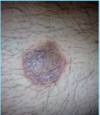

A: Describe Histology (3)

B: Dz

C: What’s the primary leukocyte in the skin

A: image

-Solar Elastosis=Grayish-bluish color of the Dermis from sun damage

B: [Actinic Keratosis-PreMalignant]

C: Lymphocyte

A: Describe Histology (3)

B: Dz

C: What’s the primary leukocyte in the skin

A: image

-Solar Elastosis=Grayish-bluish color of the Dermis from sun damage

B: [Actinic Keratosis-PreMalignant]

C: Lymphocyte